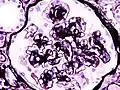

![]() Микрофотография узелкового гломерулосклероза при синдроме Киммельстил-Уилсона. | |

Синдром Киммельстил-Уилсона (диабетический гломерулосклероз) — узелковая форма гломерулосклероза, специфическая для сахарного диабета, получила название в честь патологоанатомов Киммельстил и Уилсона, обнаруживших и описавших в 1936 году своеобразное узелковое склеротическое поражение клубочков почек у лиц с сахарным диабетом. При диабете наблюдаются диффузный и узелковый варианты поражения почечных клубочков. Узелковая форма, описанная Киммельстил и Уилсоном, чаще встречается при сахарном диабете 1-го типа уже вскоре после манифестации заболевания, постепенно прогрессирует, приводя в итоге к диабетическому гломерулосклерозу и развитию ХПН. В клинической практике термином «синдром Киммелльстил-Уилсона» характеризуют нефросклеротическую, азотемическую стадию поражения почек при сахарном диабете. Последнее время этим термином пользуются реже, пользуясь диагнозом «Диабетическая нефропатия, хроническая болезнь почек 5 стадии» (Ефимов А. С. и соавт.)[3].